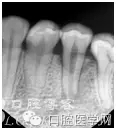

處理方案:結(jié)合X光片去判斷

處理方案:嘗試緩慢推進(jìn)銼針繼續(xù)操作,看顯示是否恢復(fù)正常,如不恢復(fù)正常,則結(jié)合X光片去判斷

處理方案:手感下不去了,即銼針尖端未能到達(dá)根尖孔,機(jī)器未能顯示到達(dá)根尖孔,結(jié)合X光片判斷

處理方案:測量不準(zhǔn)確,結(jié)合X光片去判斷